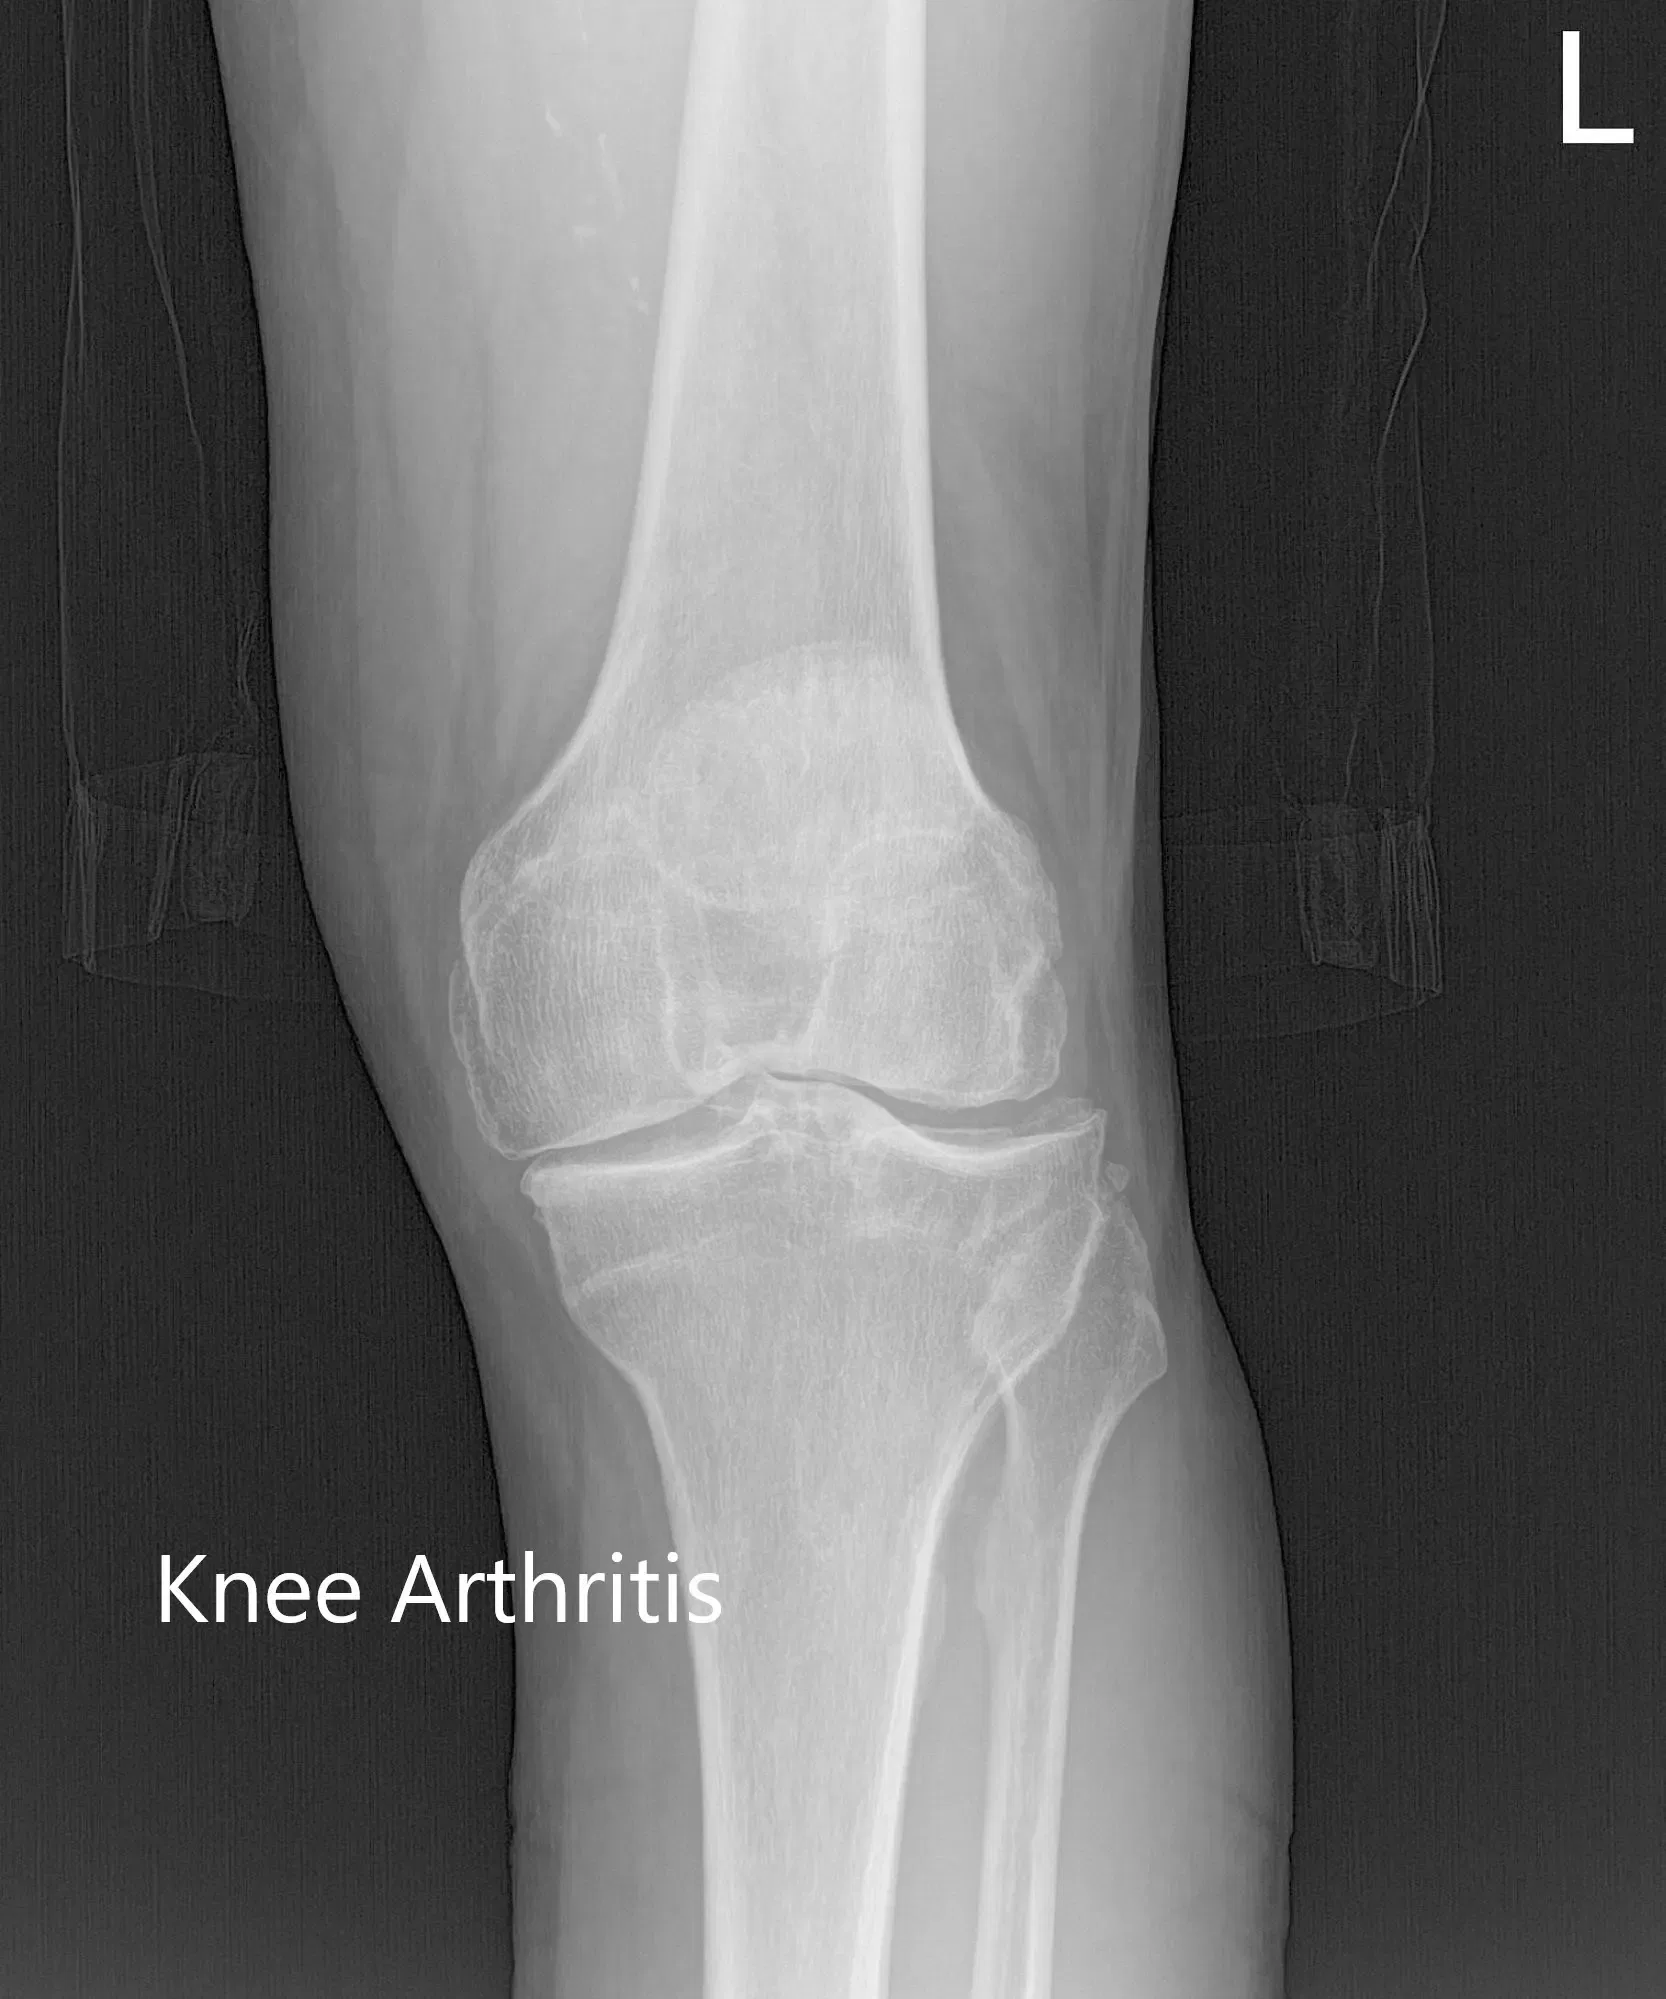

No hubo déficit neurológico distal y los pulsos bilaterales fueron de buen volumen y comparables. Los estudios de imagen revelaron una osteoartritis tricompartimental severa de la rodilla izquierda. Teniendo en cuenta el dolor de rodilla que limita el estilo de vida del paciente, se le recomendó un reemplazo total personalizado de la rodilla izquierda. Se discutieron extensamente con ella riesgos, beneficios y alternativas. Ella estuvo de acuerdo con el plan.

Radiografía preoperatoria de la rodilla izquierda que muestra las vistas AP, lateral y de la izquierda